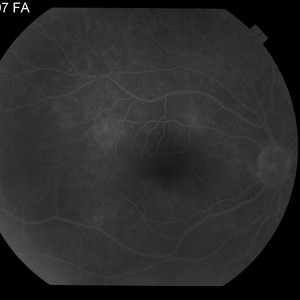

AMPPE

Apr 29 2014 by David W. Faber, MD

24-year-old female presented with central blurry vision for 3-5 days. Vision : OD 20/20, OS 20/100

Photographer: Jodi Schiele, Rocky Mountain Retina Consultants, Salt Lake City, Utah

Condition/keywords: acute multifocal placoid pigment epitheliopathy (AMPPE)